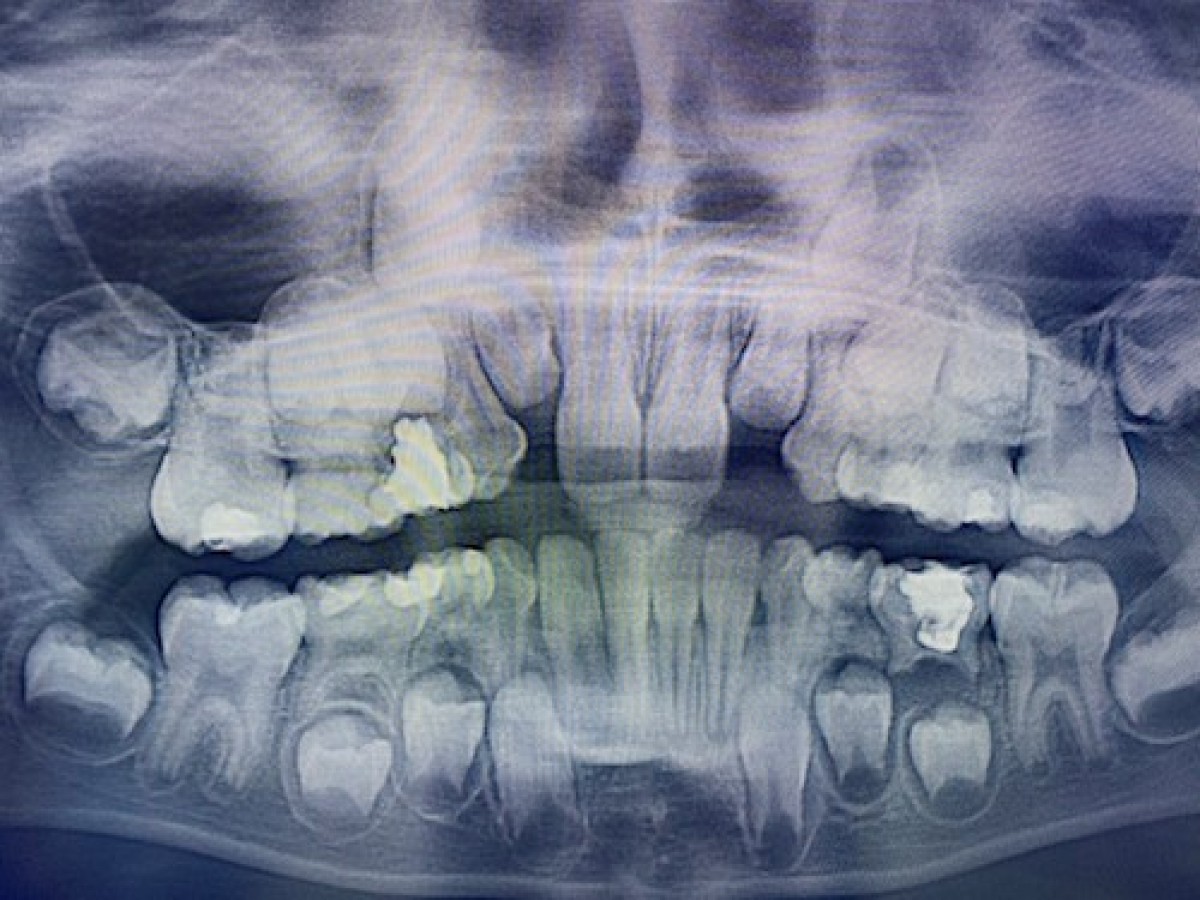

The Hall Technique: a misunderstood method against cariuous primary molars

The Hall technique (HT) is one of the methods used nowadays for biological sealing in carious lesions in primary molars, introduced in 2006 by Dr. Norna Hall. It’ s based on the use of preformed metal crowns (PMCs), placed on carious primary teeth without local anesthesia, caries removal, or tooth preparation. An appropriate size of PMCs should be chosen, then filled with glass ionomer cement and lastly fitted on thecarious primary teeth. This technique should arrest or at least reduce caries progression thanks to the modification of the plaque biofilm composition. Despite the good result highlighted in literature, the use of HT for carious primary molars remains controversial and is not yet part of the clinical routine.

The aim of this systematic review was to evaluated the outcomes of HT on carious primary teeth compared to the conventional dental restorations.

Results: Five studies were included (two RCTs, one quasi-experimental trial, and two retrospective). The total number of teeth assessed were 1775, of which 1325 teeth were restored using HT.

No difference between HT and other methods was found in the retrospective studies, whereas the RCTs and quasi-experimental showed a better effectiveness of HT over other treatment modalities. In meta-analysis, HT results significantly more effective over conventional restorations [risk ratio 5.55 (3.31-9.30)] (p value ≤ 0.001).

Conclusion: HT showed very successful results when compared with conventional restorations. Despite the predictable outcome and the fact that this treatment is simplified compared to the conventional restorative technique, the cost of materials and the operation time required may be obstacles to its adoption in common dental practice.